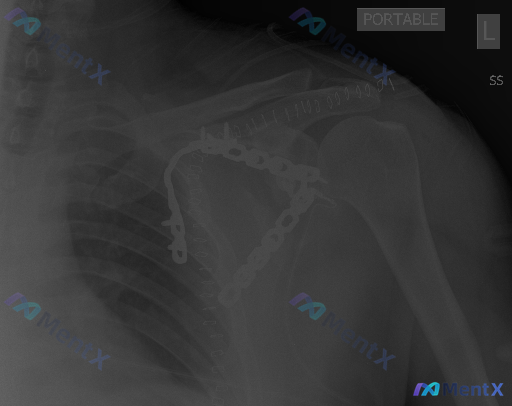

看到一张左肩部X光片,最显著的异常你会先注意到什么?

整理到一张左肩部正位X光片的读片资料,先不说最终结论,大家第一眼扫下来,会先抓住哪个核心异常?

- 骨性结构里能看到高密度的金属影

- 肱骨头轮廓是光滑的

- 关节间隙看起来没有明显的狭窄或增宽